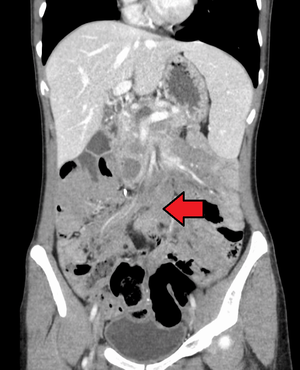

Desmoid tumor as seen on CT scan | |

Aggressive fibromatosis is a rare condition marked by the presence of desmoid tumors. Desmoid tumors can arise in virtually any part of the body, and are tumors that arise from cells called fibroblasts, which are found throughout the body and provide structural support, protection to the vital organs, and play a critical role in wound healing. These tumors tend to occur in women in their thirties, but can occur in anyone at any age. They can be either relatively slow-growing or malignant. However, aggressive fibromatosis is locally aggressive. When they are aggressive they can cause life-threatening problems or even death when they compress vital organs such as intestines, kidney, lungs, blood vessels, nerves etc. Most cases are sporadic, but some are associated with familial adenomatous polyposis (FAP). Approximately 10% of individuals with Gardner's syndrome, a type of FAP with extracolonic features, have desmoid tumors.[1]

Desmoid tumors may be classified as extra-abdominal, abdominal wall, or intra-abdominal (the last is more common in patients with FAP). It is thought that the lesions may develop in relation to estrogen levels or trauma/operations.